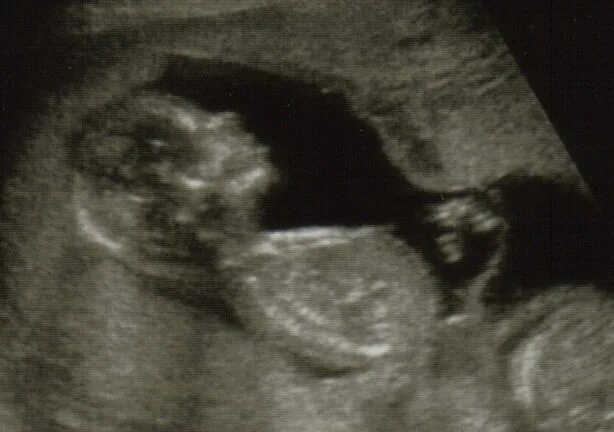

14 неделя ощущение